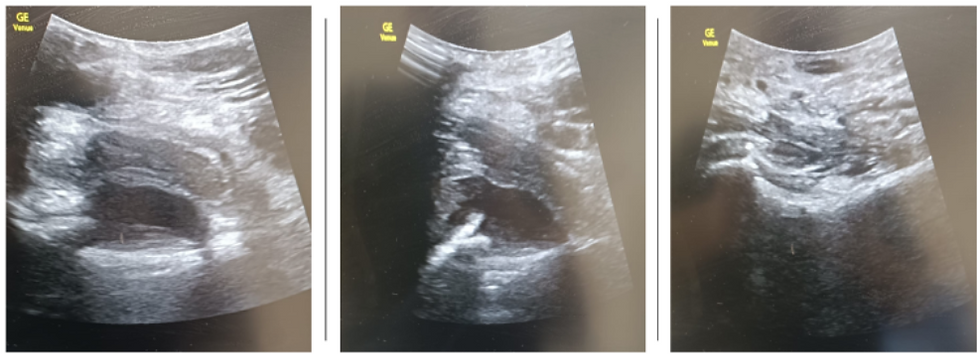

The second case involved a 30-year-old male with intravenous drug use history presenting with acute, severe right hip pain. Despite being apyrexial, he demonstrated significantly elevated inflammatory markers (CRP 180 mg/L, WCC 18 × 10⁹/L). POCUS identified a 2.5 × 3 cm fluid collection in the right hip joint. Likely differentials were joint effusion or infected psoas bursa. POCUS also demonstrated bilateral calf abscesses at the injection site. Proximal deep vein thrombus was excluded on bilateral legs by POCUS.

Right hip transverse view: Demonstrates effusion

Right hip longitudinal view: Demonstrates effusion

Left hip longitudinal view: No effusion